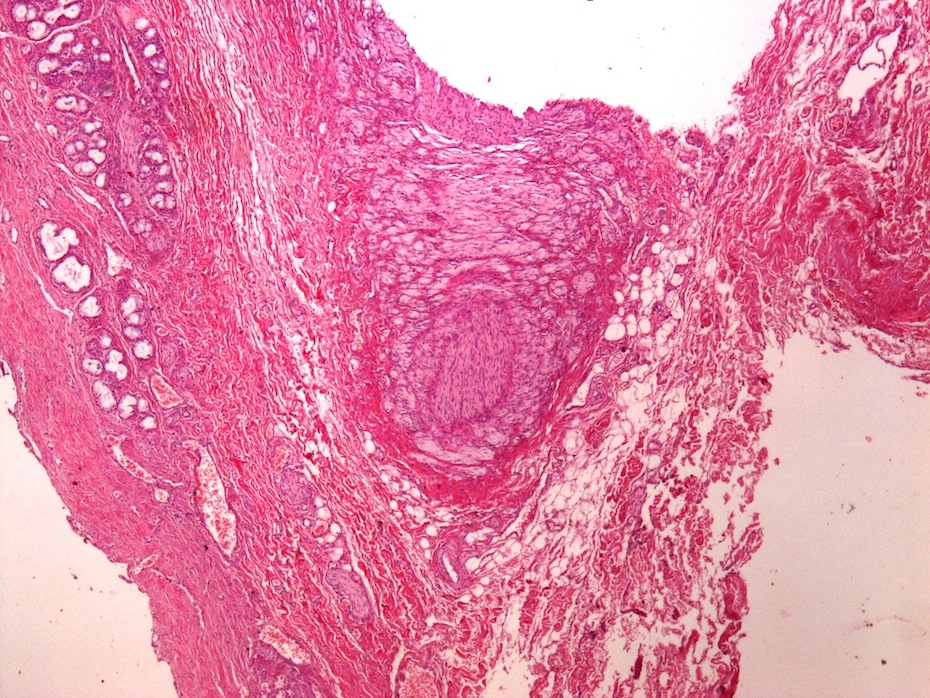

Microscopic images:

Microscopic images:

Both cases showed disorganized and thickened nerve bundles composed of spindle shaped cells, without atypia. Case A also showed a focal foreign body type giant cell reaction adjacent to the disorganized nerve bundles and a strongly immunoreactive S100 stain.

Histology typically shows hyperplastic nerve bundles, positive for S100.

Both cases showed disorganized and thickened nerve bundles composed of spindle shaped cells, without atypia. Case A also showed a focal foreign body type giant cell reaction adjacent to the disorganized nerve bundles and a strongly immunoreactive S100 stain.

Histology typically shows hyperplastic nerve bundles, positive for S100.